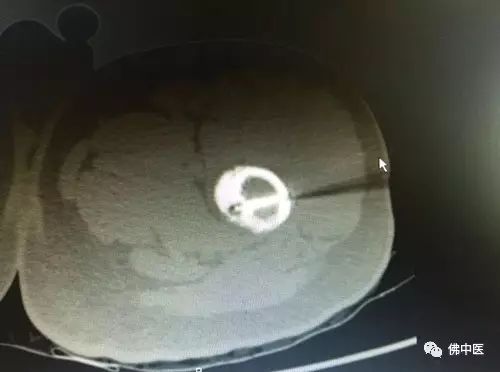

术中CT照片

CT引导下经皮穿刺射频消融术是近几年发展的微创新技术,其创伤少,能明显降低骨折、感染等风险;同时,该技术借助CT引导,能准确地定位瘤巢,经皮穿刺直达病灶,其后把冷循环单电极置入瘤巢中心,对病灶及周围约1.2cm组织进行连续射频消融。据劳永锵介绍,消融中心温度可高达90℃,持续或间断作用5-10分钟后,可对病灶进行热损毁,从而保证治疗效果。“这种术式一次治愈率约90%,复发病例二次治愈率可达100%。该技术的成功引进,将给患者带来更好的治疗体验和更安全的治疗效果。”